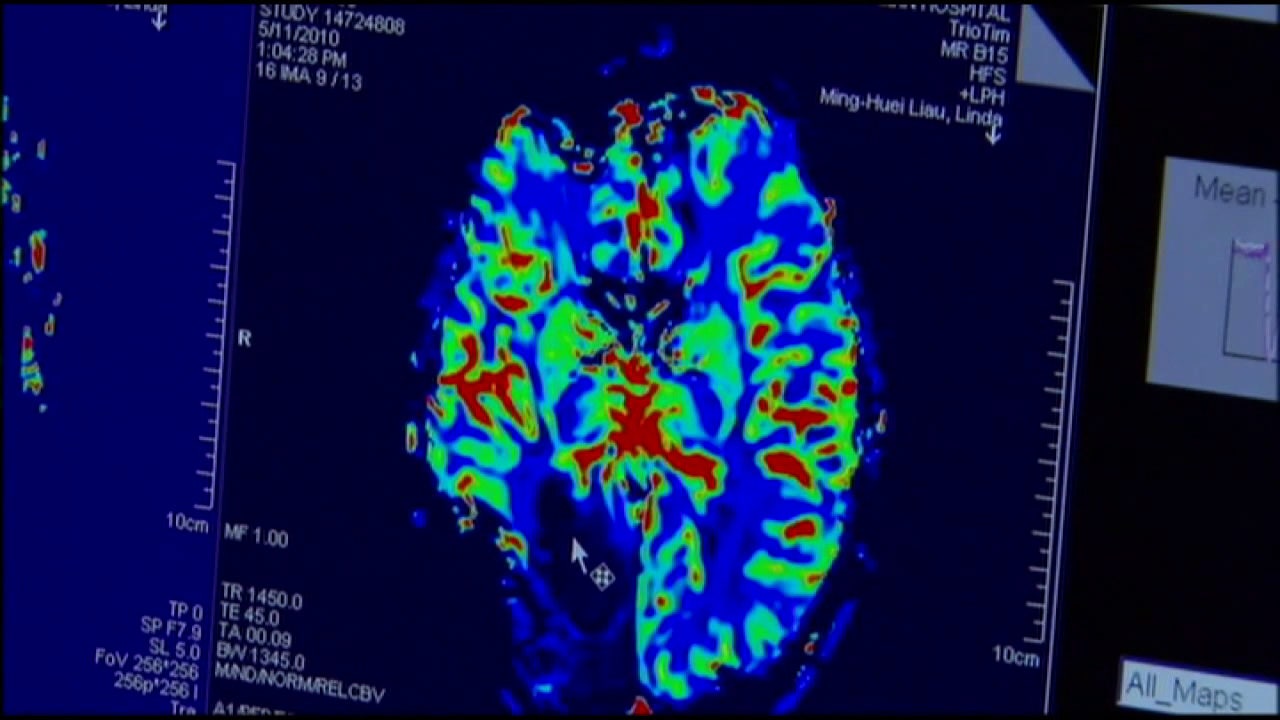

TAMPA, Fla. - The FDA has approved a new drug called Modeyso for the treatment of diffuse midline glioma (DMG), a rare and aggressive brain and spinal cord cancer.

DMG impacts about 200 to 300 people in the U.S. annually, mostly children and young adults. The drug is usually taken once a week in pill form, offering an alternative to risky surgeries and radiation treatments.

Dr. Patrick Grogan of Tampa's Moffitt Cancer Center said this is a milestone for brain tumor treatment. Historically, very few drugs have been approved for these types of tumors.

DMG survival rates are typically less than a year, and treatment options have been extremely limited. Modeyso offers patients not just more time, but potentially better quality of life by reducing the need for invasive procedures.